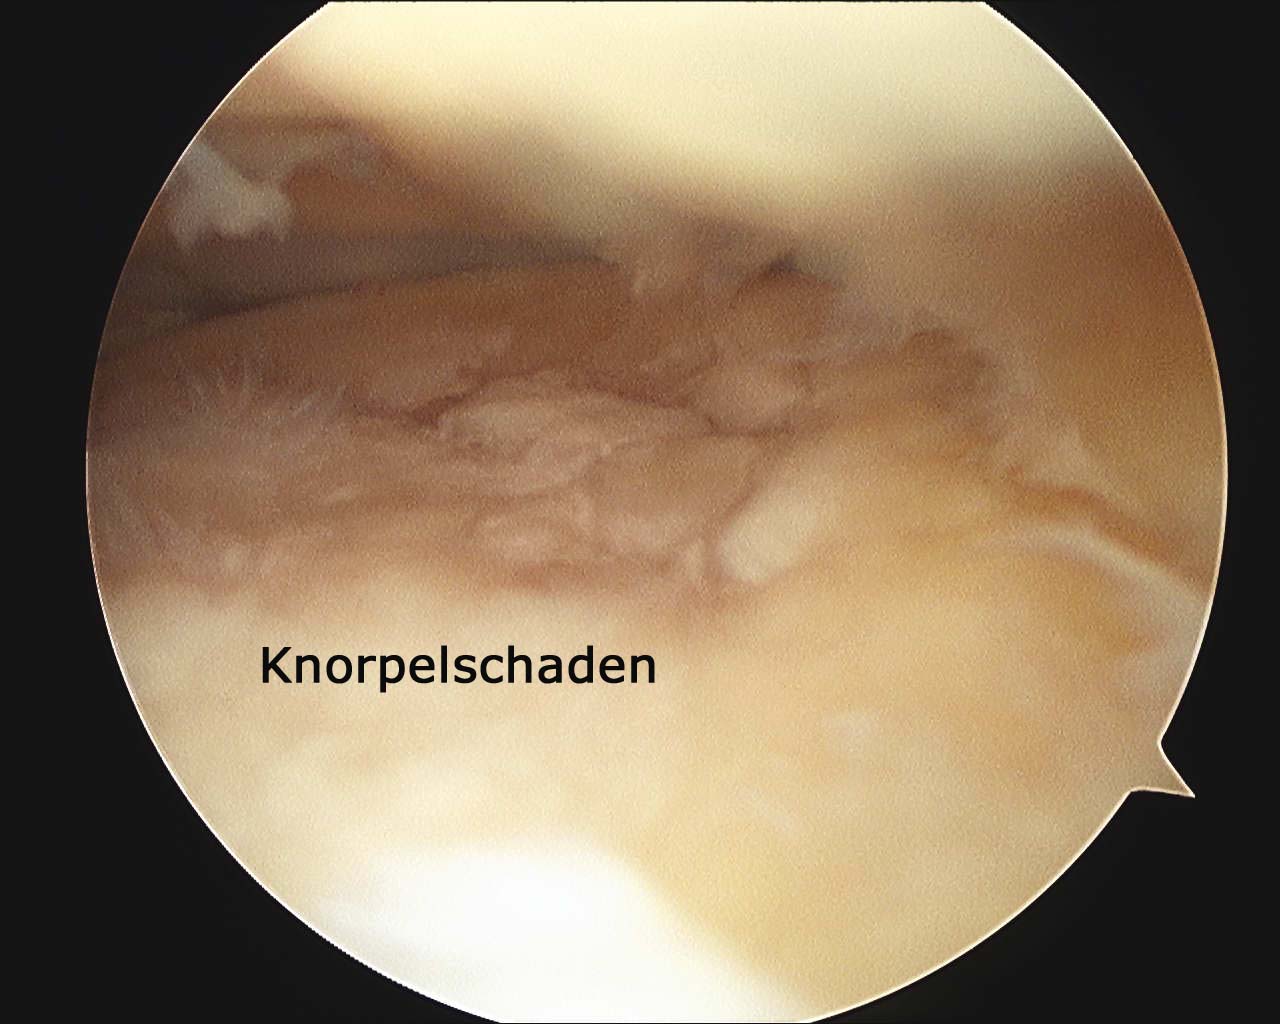

Arthroskopie

Bei Nichtansprechen der konservativen Therapiemaßnahmen können in Fällen mit noch geringer radiologischer Veränderung und guter  Beweglichkeit  der betroffenen Gelenke weitere, dann jedoch invasiver Maßnahmen zur Therapie erforderlich sein.  So kann sowohl bei Hüfte als auch Kniegelenk eine arthroskopische Operation – also ein wenig invasiver Eingriff – die Schmerzen dauerhaft lindern.